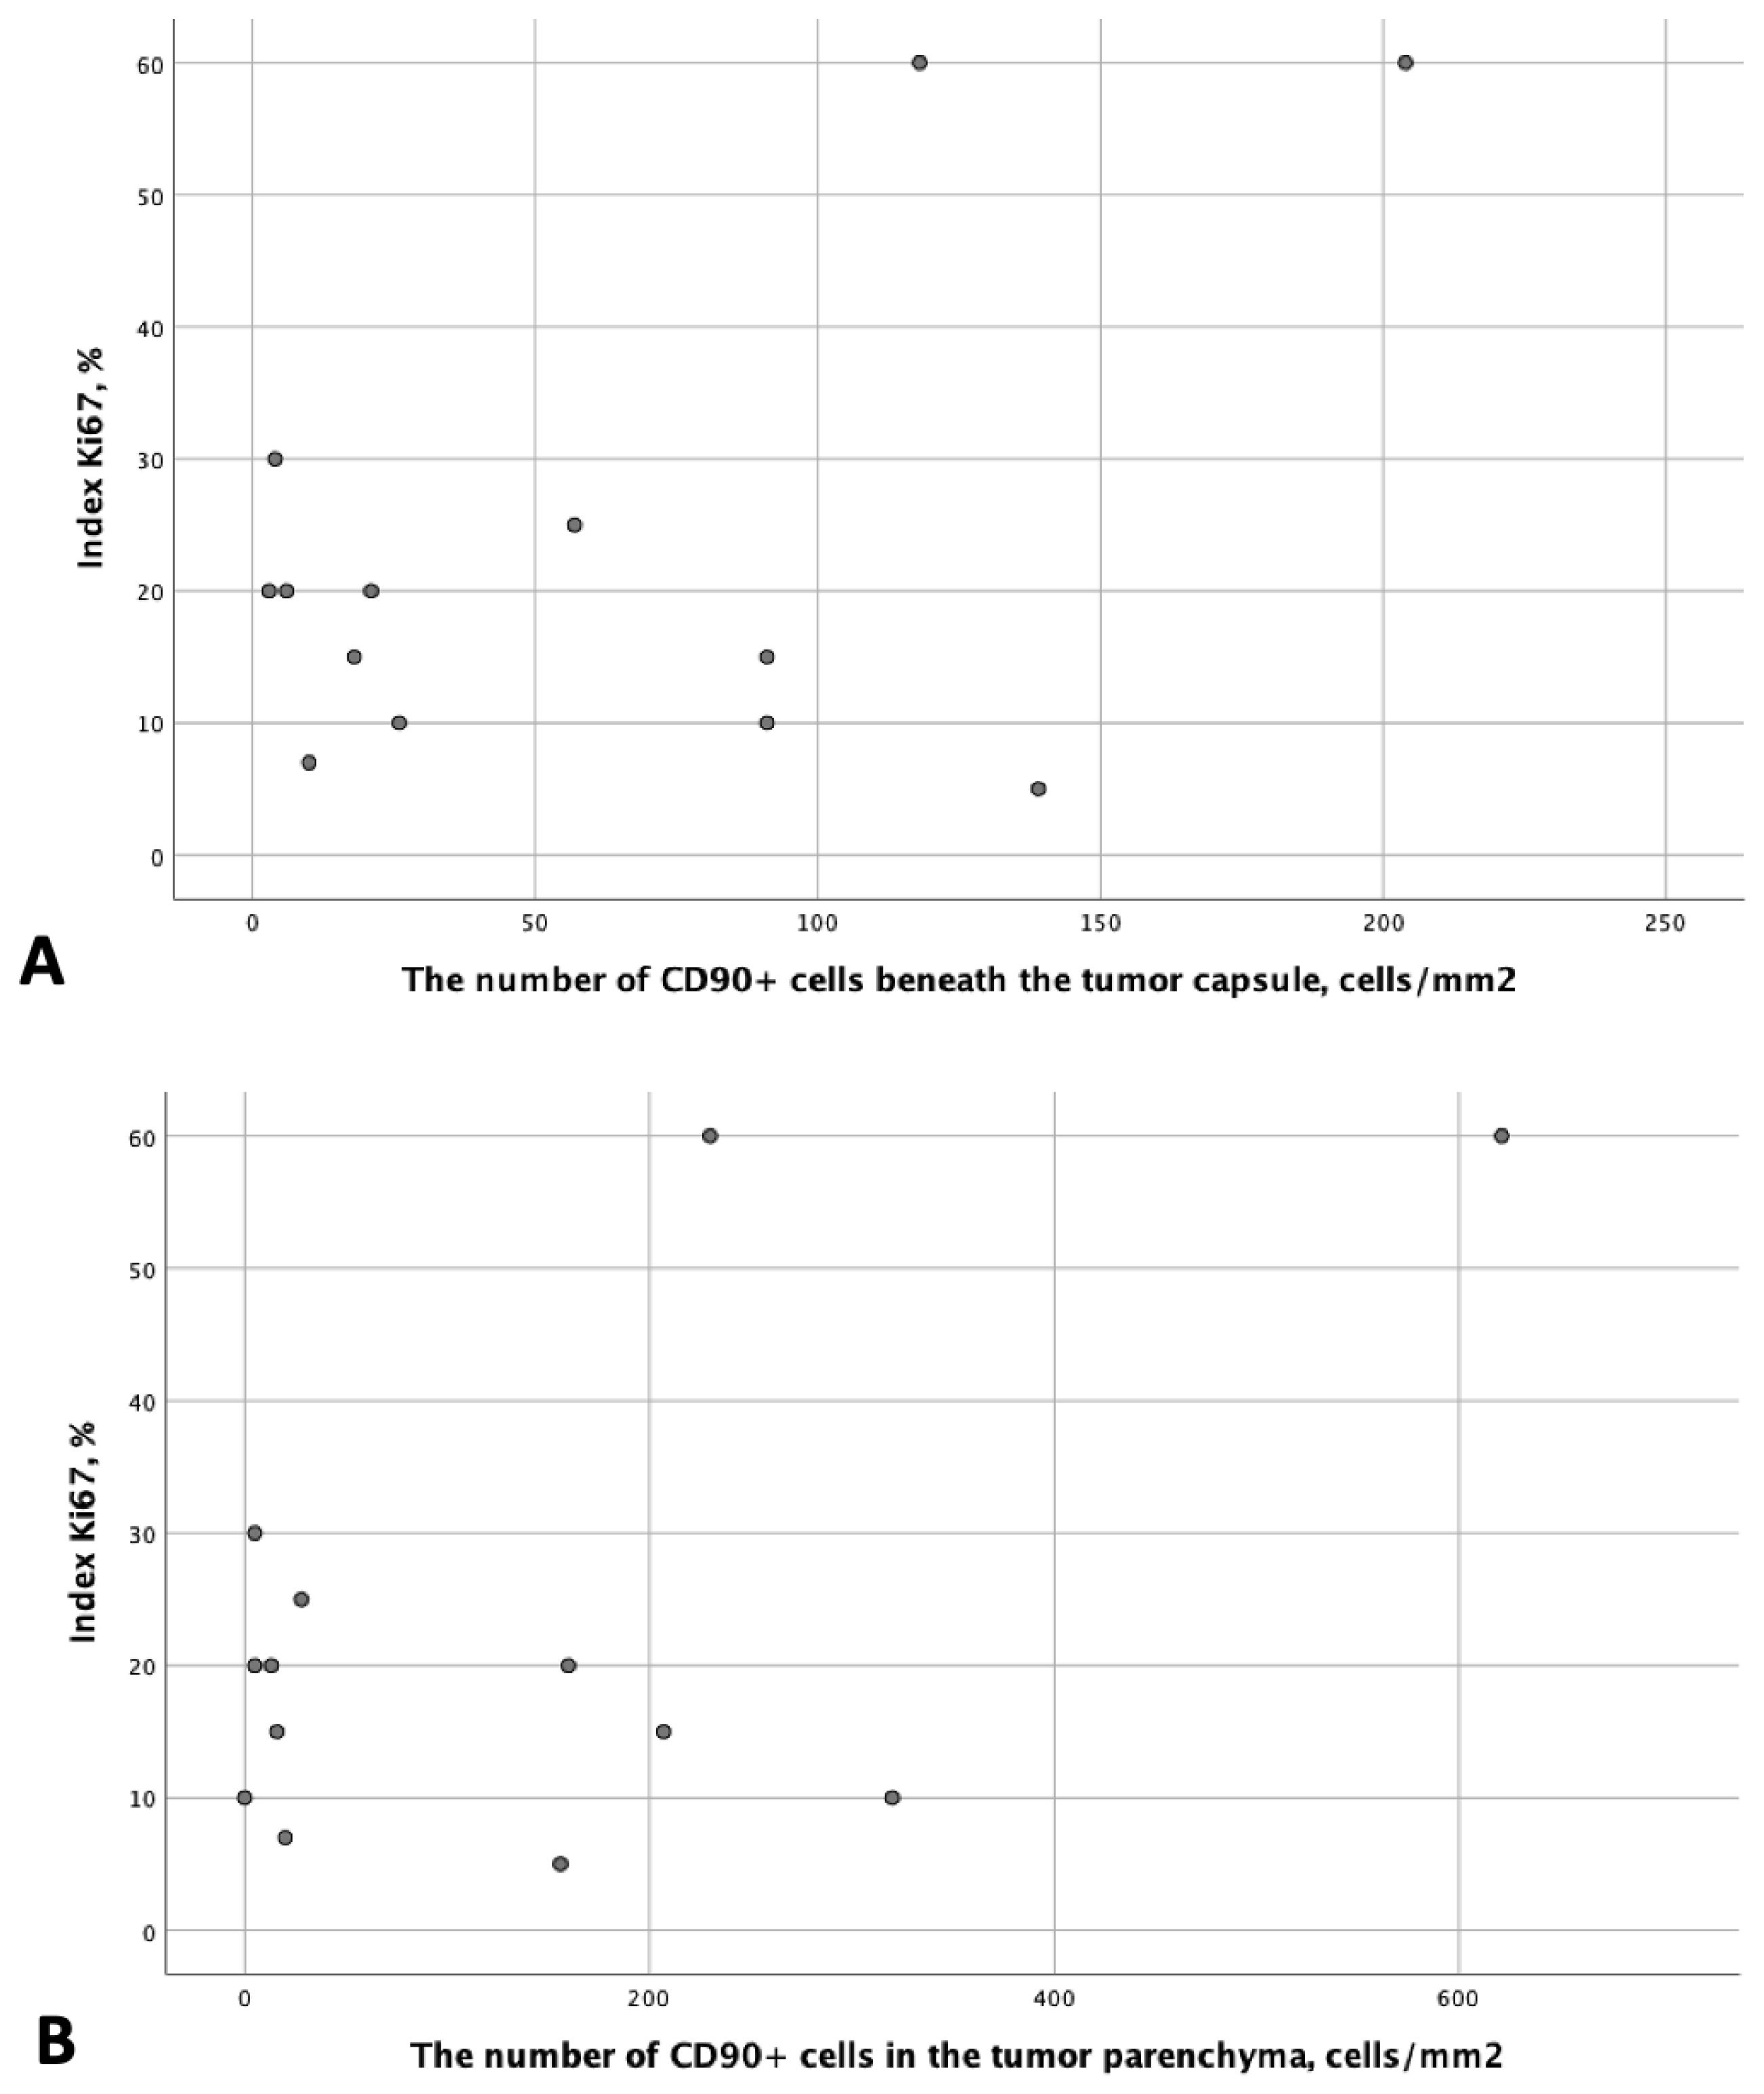

3.1. Analysis of CD90 Marker Expression

3.3. Analysis of Patient Survival Depending on the Expression of Stem Markers